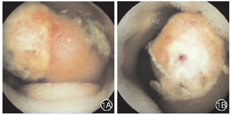

患者男,34岁,因"便血1 d"急诊入院。入院前1 d无明显诱因解暗红色糊状便2次,总量约600 mL,伴头晕、乏力,无腹痛、恶心,无晕厥、黑矇等。否认消化性溃疡、慢性肝炎病史,无非甾体消炎药等药物服用史,无吸烟、饮酒等不良嗜好。入院查体:体温36.3℃,脉搏83次/min,呼吸18次/min,血压114/65 mmHg(1 mmHg=0.133 kPa),贫血貌,睑结膜苍白,皮肤巩膜无黄染,未见肝掌、蜘蛛痣,心肺未见异常体征,腹软,全腹无压痛及反跳痛,肝脾肋下未触及,肠鸣音活跃(约10次/min)。实验室检查:血红蛋白79 g/L、红细胞比容0.225、血小板227×109/L;便潜血(+);肝功能、肾功能、凝血功能及肿瘤标记物均正常。胃镜检查结果:慢性非萎缩性胃炎。结肠镜检查结果:正常结肠黏膜,回肠末段肠液呈洗肉水样。胶囊内镜检查结果:回肠中段见一结节样肿物,表面充血、糜烂(图1)。患者胃肠镜检查均未见明显出血病灶,结合胶囊内镜检查结果及病情,考虑小肠病变致消化道出血可能性大,遂转外科行开腹手术以明确出血原因及部位。术中见:距离回盲部约55 cm处小肠壁见一大小约2 cm×2 cm肿物,病灶处肠壁血管增多并轻度曲张(图2),行小肠病损切除术。术后病理提示小肠胰腺异位Ⅰ型(图3)。患者术后血红蛋白稳定上升,出院随访至今无便血现象。